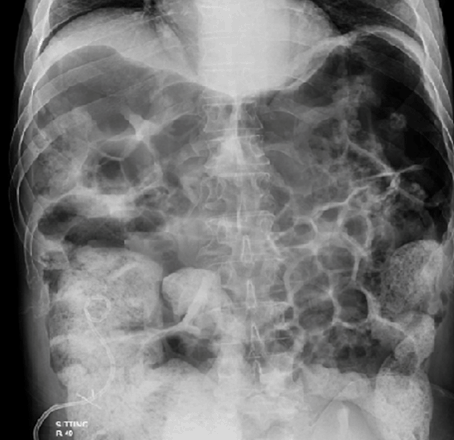

X-ray of the abdomen (erect and supine) showed the appearance of extensive colonic gaseous distention that raised both diaphragmatic leaflets. Colonic liquefied fecal content was seen extending down to the rectum. Overall impression on imaging was of pseudo-obstruction (Figure 1). Computed tomography (CT) scan of abdomen with contrast showed marked diffuse colonic dilation with no evidence of a mechanically obstructing lesion (Figure 3) And (Figure 4).

Figure 1: Supine abdominal X-ray on admission (Cecum approximately 9 cm).